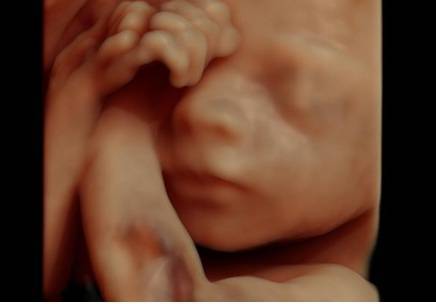

Grazie a un nuovo ecografo infatti, il Voluson E10 creato dalla General Electric sarà possibile seguire gli spostamenti del piccolo anche in movimento.

Il nuovo software così consentirà non solo di osservare l’aspetto tridimensionale del piccolo ma di poter anche ottenere, in pochi secondi, immagini dei vasi sanguigni, degli organi e del cuore.

Si tratta quindi di un’importante innovazione per monitorare la crescita e la salute del bambino durante il primo trimestre di gravidanza.

Come già dimostrato da uno studio sugli effetti del fumo sul feto realizzato con ecografie 4D questa tecnologia potrebbe diventare molto utile per la medicina.